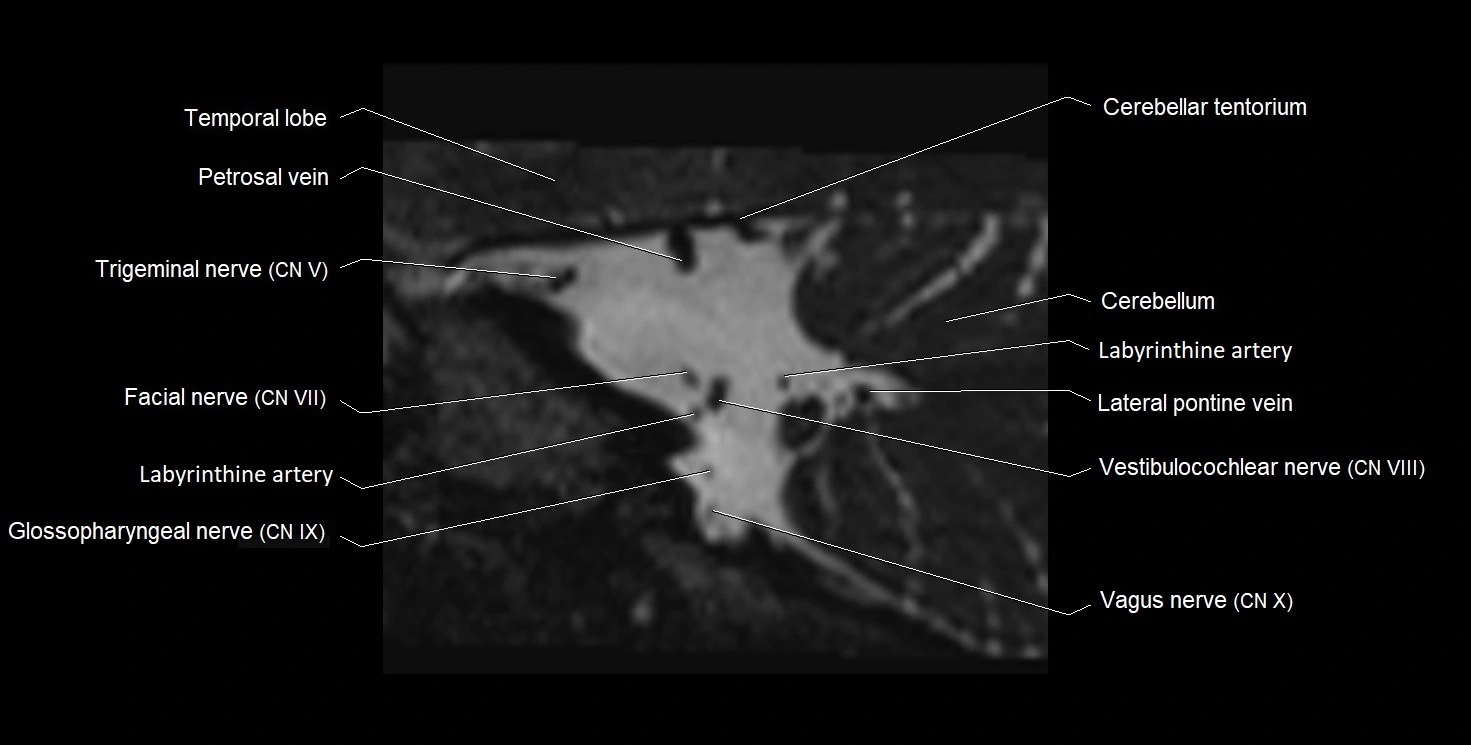

MRI Appearance

• The abducens nerve is a small, thin, linear structure

• Best visualized on high-resolution T2-weighted 3D MRI sequences (e.g., FIESTA or CISS)

• Seen as a hypointense (dark) line running from the brainstem at the pontomedullary junction, traversing the prepontine cistern, and entering Dorello’s canal under the petrosphenoidal ligament, then into the cavernous sinus, and finally the orbit

• May be challenging to visualize in standard MRI due to its small size

• Pathology may be inferred by absence, displacement, or enhancement of the nerve

MRI images

image